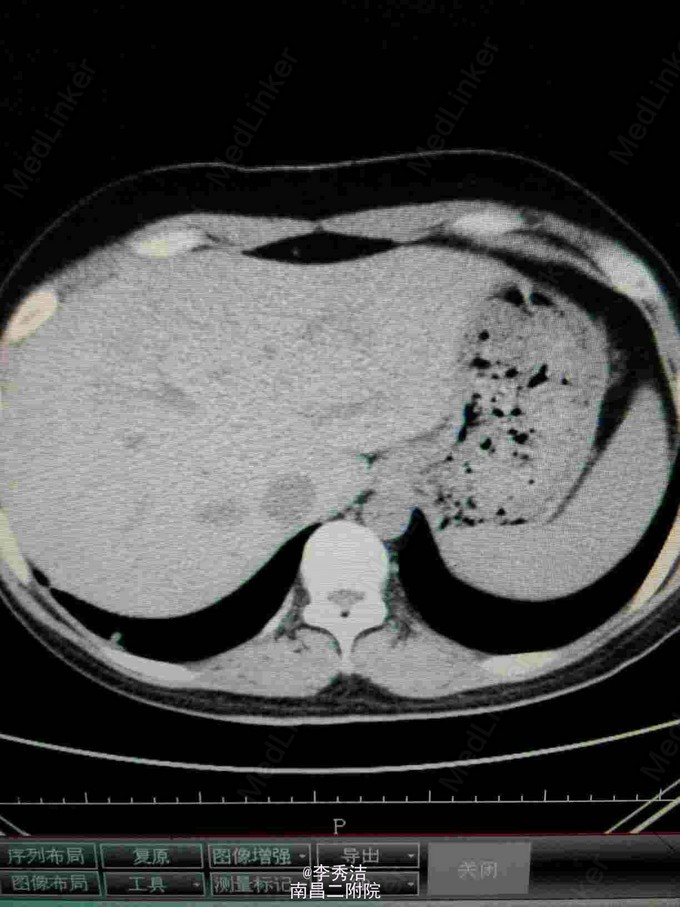

患者女,24岁,因“产后阴道不规则出血4月,发现妊娠滋养细胞肿瘤5天”入院。 患者于2014年12月11日足月自阴道分娩一胎儿(死胎)。后因阴道流血不尽,于2015年2月4日至当地医院清宫,未送病检。于2015年3月7日阴道血未干净至外地医院行第二次清宫,送病理报告示:(宫腔内刮出物)血块中见显著增生滋养叶细胞,核异形明显,考虑滋养叶细胞肿瘤,另见少量蜕膜组织。自诉6天前因阴道出血量多,明显多于月经量,至当地医院行阴道壁修补术。现无阴道流血,稍感下腹部隐痛,无头痛、发热等不适。门诊拟“阴道流血原因待查:滋养叶细胞肿瘤?”收入院。患者自发病以来,精神食欲睡眠可,大小便正常,体重无明显变化,否认高血压、糖尿病等慢性病史;否认传染病史;无食物药物过敏史,无手术及外伤史。平素月经规律,4~6天/33天,末次月经2014年3月26日,量中活动,暗红,有痛经,无血块。已婚,妊娠2,足月顺产2(1为死胎),未避孕。 查体:生命体征平稳,心肺听诊未及异常,腹平软,无压痛及反跳痛。妇检:外阴:已婚已产式;阴道:畅软,内见少量暗红色血液,前壁见两针丝线缝合;宫颈:光滑;宫体:平后位,超鸭蛋大小,质中、活动、无压痛;双附件未及异常。 辅助检查:2015年3月19日外院病理报告示:(宫腔内刮出物)血块中见显著增生滋养叶细胞,核异形明显,考虑滋养叶细胞肿瘤,另见少量蜕膜组织。血HCG209675mIU/ml。胸部CT示:肺部转移病灶。我院彩超示:子宫内混合回声团块,考虑滋养细胞肿瘤。 诊断:绒毛膜癌III期 诊疗计划:考虑患者为高危,使用联合化学药物治疗,5-FU+国产放线菌素D(更生霉素 KSM)。使用方法:5-FU 26~28mg/(Kg. d)+KSM6ug/(Kg. d)。静脉注射8天,每周检测血HCG水平一次。间隔13天进行第二次化疗。停药指证:HCG连续三次阴性后,继续给予三个疗程化疗。